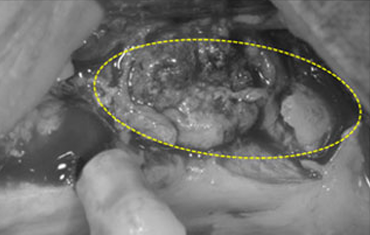

윗턱뼈 공기주머니에 뼈이식

치료 전